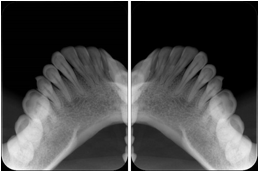

- OO-1. Intra-oral Full Mouth Series Structured Display